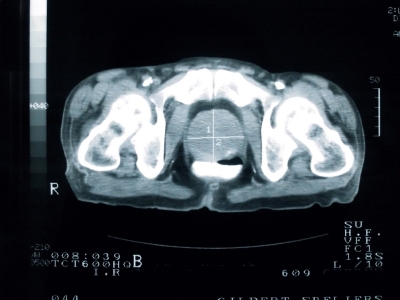

Изучение истории болезни и медицинский осмотр не проводятся. Испытания проводятся для установления диагноза и степени заболевания и могут включать: моча или предстательной железы цитологию жидкости, биопсия простаты, сканирование костей, позитронно Tomagraphy выбросов (ПЭТ). Выборочная проверка доступны и включают в себя: PSA и AMACR (генетических маркеров).

Медицинские процедуры, проводимые при заболевании рак предстательной железы: УЗИ брюшной полости, Биохимический анализ крови, Клинический анализ крови, Спиральная компьютерная томография, Анализ мочиЛЕЧЕНИЕ И ПРОФИЛАКТИКА